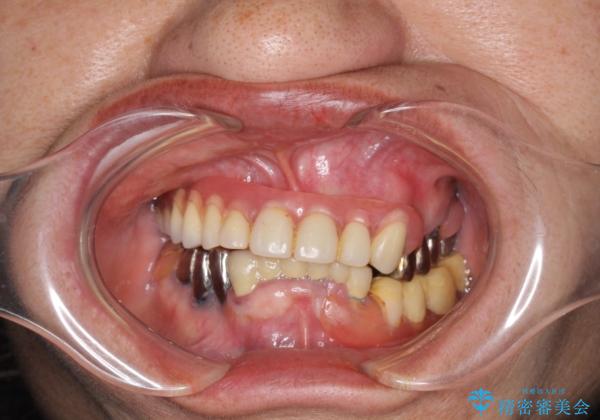

インプラントオーバーデンチャー 咬合平面の改善

- 他院にて入れ歯を入れたが全体的に左に傾いており、咬みにくく、見た目も気になるといらっしゃった方の症例です。

診査の結果、虫歯が進行し保存できない歯が多かったため抜歯し、磁性アタッチメントを用いたインプラントオーバーデンチャーによる咬合及び見た目の改善を行いました。